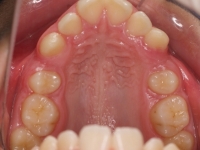

La paciente O.O. acude a nuestra consulta por:

– Canino 13 e incisivo lateral 42 en posición ectópica.

– Canino 23 incluido.

Con lo que decide realizarse un tratamiento de ortodoncia de duración de 24 meses con brackets damon Q.

CASO COMPLETO: